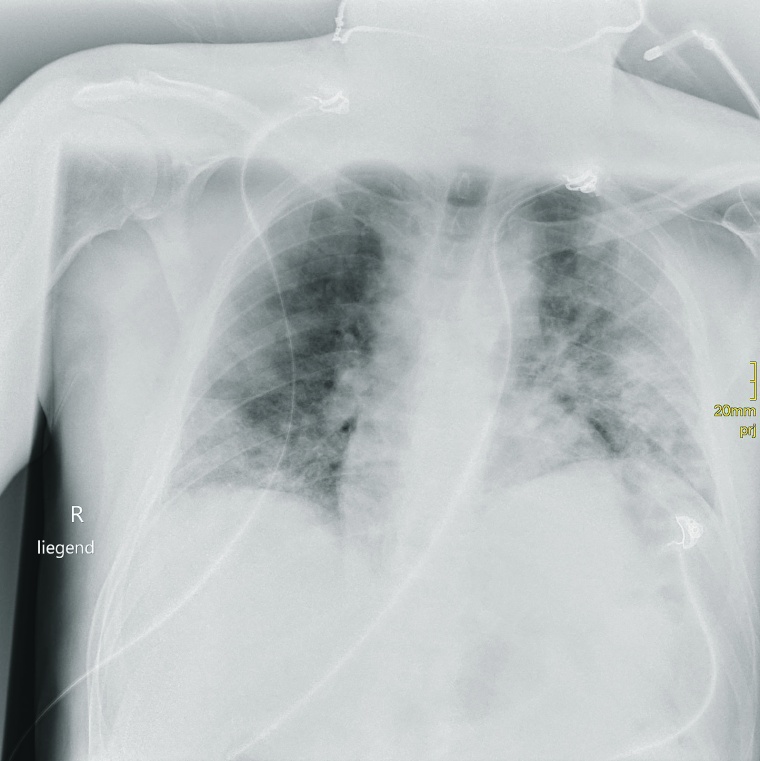

Prof. Dr. Stephan Kloska: Durch unsere sehr aktive Notaufnahme haben wir einen großen Anteil an Patienten mit eingeschränkter Mobilität und nachts ist manchmal nur eine MTRA im Einsatz. Darum brauchen wir ein System, bei dem die Patienten einfach und auch von einer Person alleine umgelagert werden können. Da kommt uns die Funktionalität des Adora-Systems, bei dem keine Umlagerung in der 2. Ebene erforderlich ist, sehr entgegen. In der ersten Pandemiewelle wurden rund 50 % der COVID-19-Fälle der Region im Klinikum Fürth behandelt, in Hochzeiten waren es bis zu 90 stationäre Patienten. Gerade in dieser Phase, wo der Andrang mit Patienten auf COVID-Verdacht ausgesprochen groß war und ist und wir schnell nach COVID-Patienten und Verdachtsfällen vorsortieren mussten, konnten wir mit dem Adora-System in der Notaufnahme sehr schnell agieren.

Kloska: Grundsätzlich kann man sagen, dass es die Überlegungen, auf ein volldigitales System umzusteigen, schon länger gab. Aber Corona hat die Anschaffung noch einmal maßgeblich beschleunigt.